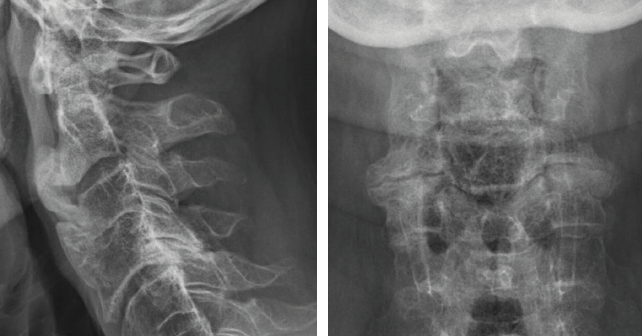

Revu quatre semaines plus tard, le patient déclarait avoir été amélioré de manière modérée par la prednisolone et ne prenait maintenant que du paracétamol à la demande. L’état douloureux persistait mais de manière à nouveau atténuée. Sur la nouvelle IRM lombaire, l’aspect était inchangé, notamment sans anomalie de type tumoral. Les radiographies de la charnière dorsolombaire et du rachis lombaire montraient de nombreux ponts vertébraux prédominant à droite, avec des aspects de pont ostéophytique hypertrophique mais aussi des ponts très peu épais de type syndesmophytique notamment en T12-L1 de face (Figures 4a, 4b et 4c). Les radiographies du rachis cervical objectivaient de volumineuses ossifications prévertébrales, très épaisses, aux étages C2-C3, C3-C4 et C5-C6, ainsi qu’une importante arthrose interapophysaire postérieure C4C5 bien visible de face (Figures 5a et 5b). Sur la scintigraphie osseuse au technétium 99m, il y avait de nombreuses hyperfixations siégeant uniquement à des sites d’ostéophytes et de ponts intervertébraux, au rachis lombaire des deux côtés et au rachis thoracique haut, surtout à droite (Figures 6a et 6b). L’ensemble des résultats et le recul permettait d’éliminer des lésions tumorales, de réfuter le diagnostic de spondyloarthrite et de confirmer la responsabilité de l’HVE dans cette poussée douloureuse axiale. Le patient était rassuré et nous prescrivions du paracétamol à la demande.

Figures 5a et 5b. Radiographies du rachis cervical de profil et de face.